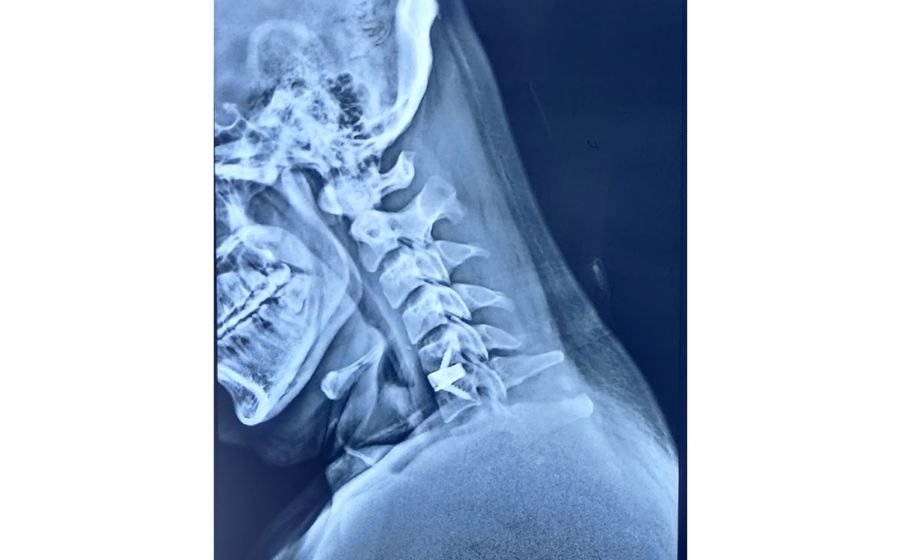

Cervical Disc Replacement (Cervical ADR)

Cervical disc replacement is an advanced alternative to fusion for select patients with disc herniation or degeneration in the neck. Instead of fusing the bones, the damaged disc is removed and replaced with an artificial disc that preserves natural neck motion. This maintains mobility while relieving pressure on the nerves and spinal cord. ADR is designed to reduce pain, improve function, and lower the risk of adjacent level degeneration in the long term.